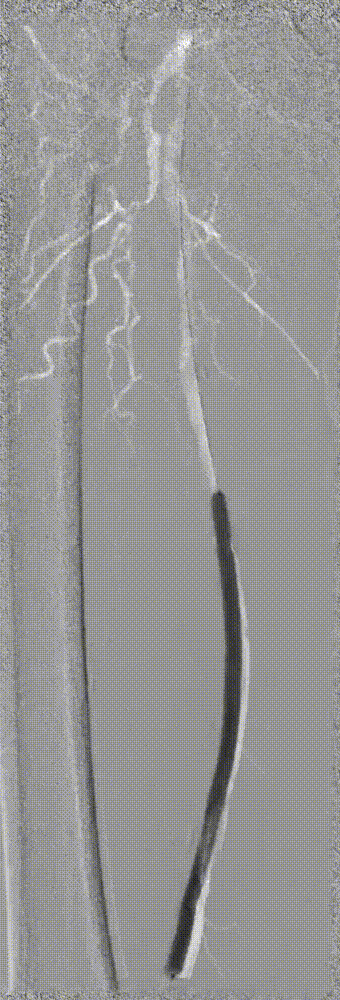

因患者股浅动脉及腘动脉狭窄闭塞段均严重钙化,选择使用振波球囊(6mm*80mm、5mm*80mm)

分别对股浅动脉、腘动脉狭窄闭塞段扩张(球囊至4atm,3级振波强度3个循环,5级振波强度3个循环);球囊切迹逐渐消失

步进造影配合血管腔内超声诊断导管提示:股浅动脉全程、腘动脉、胫腓干动脉血流通畅,未见明显夹层、造影剂外溢,远端未见栓塞,膝下动脉如前。